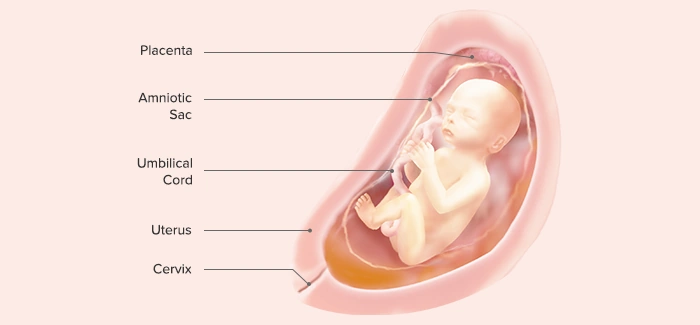

Ultrasound at 24 Weeks: What Is Checked?

⭐ Ultrasound at 24 Weeks: What Is Checked?

A growth scan or detailed ultrasound at this stage may evaluate:

1. Baby’s Measurements

• Head circumference (HC)

• Abdominal circumference (AC)

• Femur length (FL)

• Estimated fetal weight (EFW)

2. Organ Development

Assessment of:

• Heart structure and heartbeat

• Kidneys, bladder

• Stomach, intestines

• Lungs

• Spine and limbs

3. Fetal Movements

Observing:

• Limb movements

• Breathing motions

• Opening and closing of hands

4. Placenta

• Location (anterior, posterior, low-lying)

• Thickness

• Blood flow (Doppler if needed)

5. Amniotic Fluid Level (AFI)

6. Cervical Length (if needed)

For mothers at risk of preterm labor.